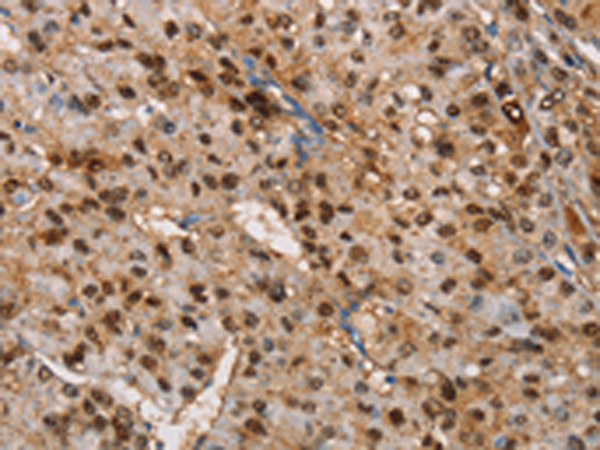

分类: 科研抗体货号: P08018别名: MSS4; STM7应用: IHC反应种属: Human, Mouse, Rat